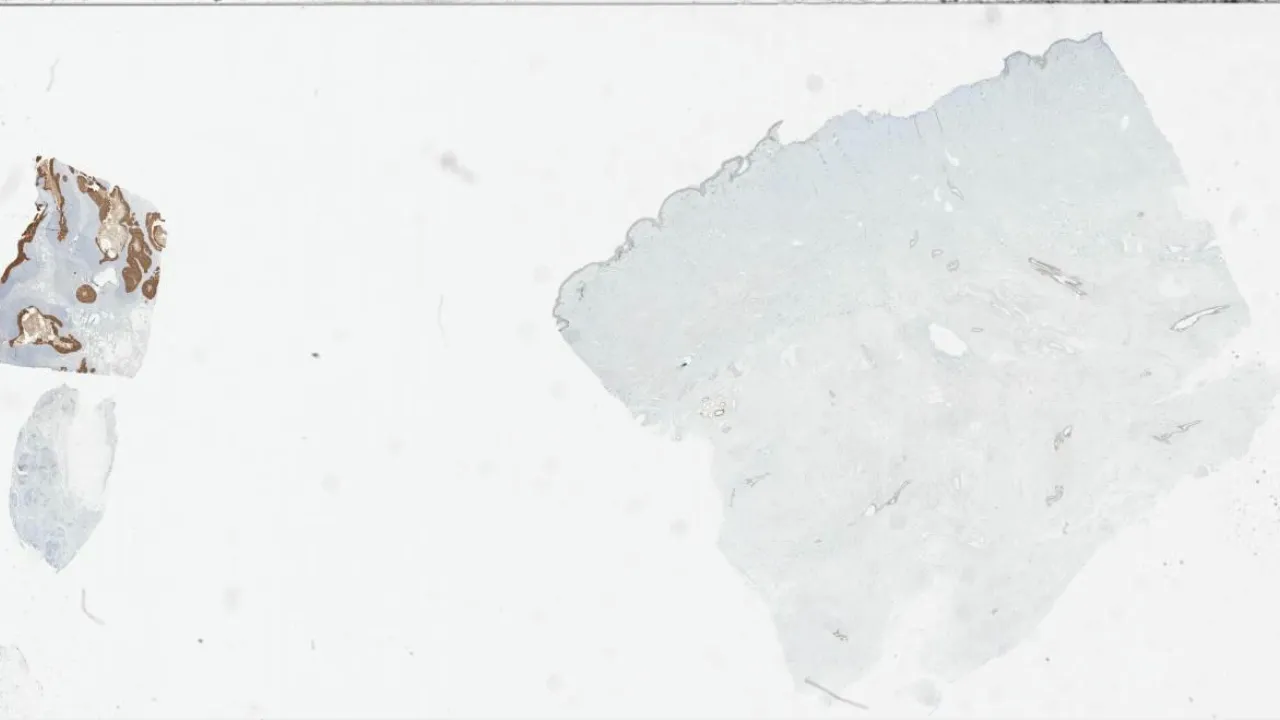

Skin, Subcutaneous Fat Necrosis